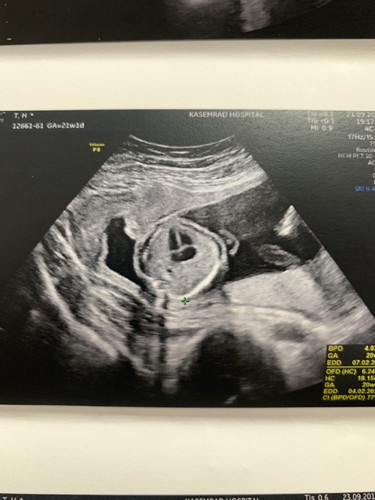

ผนังกั้นหัวใจตอนอยู่ในครรภ์ 21 w

ตั้งครรภ์ได้ 21 w ภาพอัลตร้าซาวน์นี้เป็นการดูผนังกั้นหัวใจทั้ง 4 ห้อง แต่น้องมีผนังกั้นหัวใจ แค่ 3 ห้อง ยังมีโอกาสปิดครบ 4 ห้องมั้ยคะ ลูกบ้านไหนเป็นแบบนี้บ้าง มีภาพมาขอดูหน่อยค่ะ

ตอนซาวด์หมอบอกว่ายังใงบ้างคะ